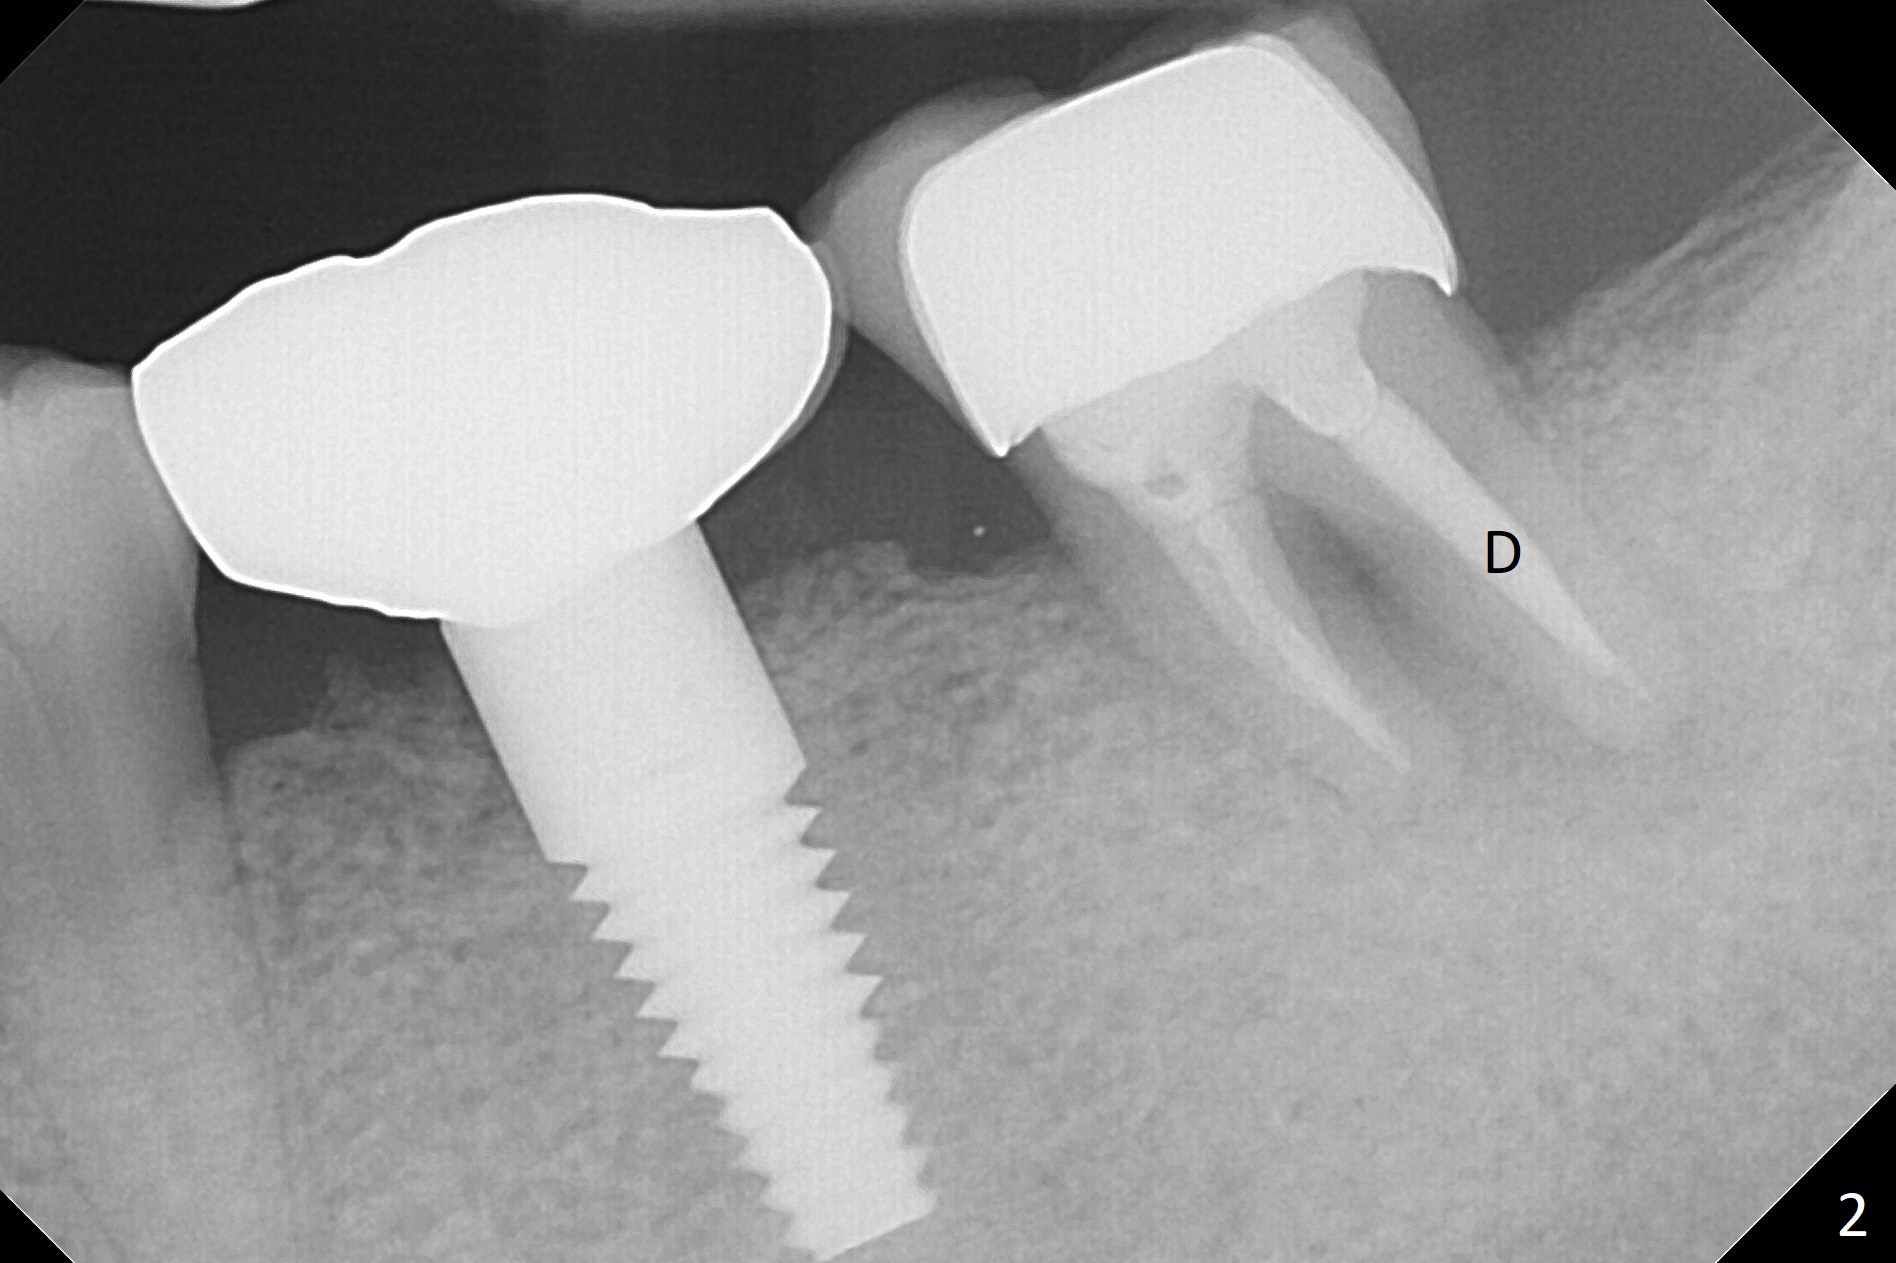

Due to severe furca (Fig.1 *) and distal root (Fig.2 D) infection at #31, there is pain when osteotomy is initiated in the apical native bone for 2 mm after extraction (Fig.3). The distal root is found to have vertical fracture. Socket preservation is performed with Vera Graft, collagen plug and 6-month membrane (Fig.4). In fact it would be possible to initiate osteotomy (Fig.5 white line) in the mesial slope (red dashed line) for implant placement (less infection (far from the lesion), less pain). There is postop pain and swelling, but the symptoms are less 7 days postop (Fig.6). The patient returns 6 months post socket preservation (Fig.7). The bone density at the healed socket is high (>1000 units); a 5x10 mm implant will be placed with guide (Fig.8). After implant placement at #18, make a buccal incision to explore the buccal gingival defect at #19 (Fig.9, 1), most likely due to extra bone graft.